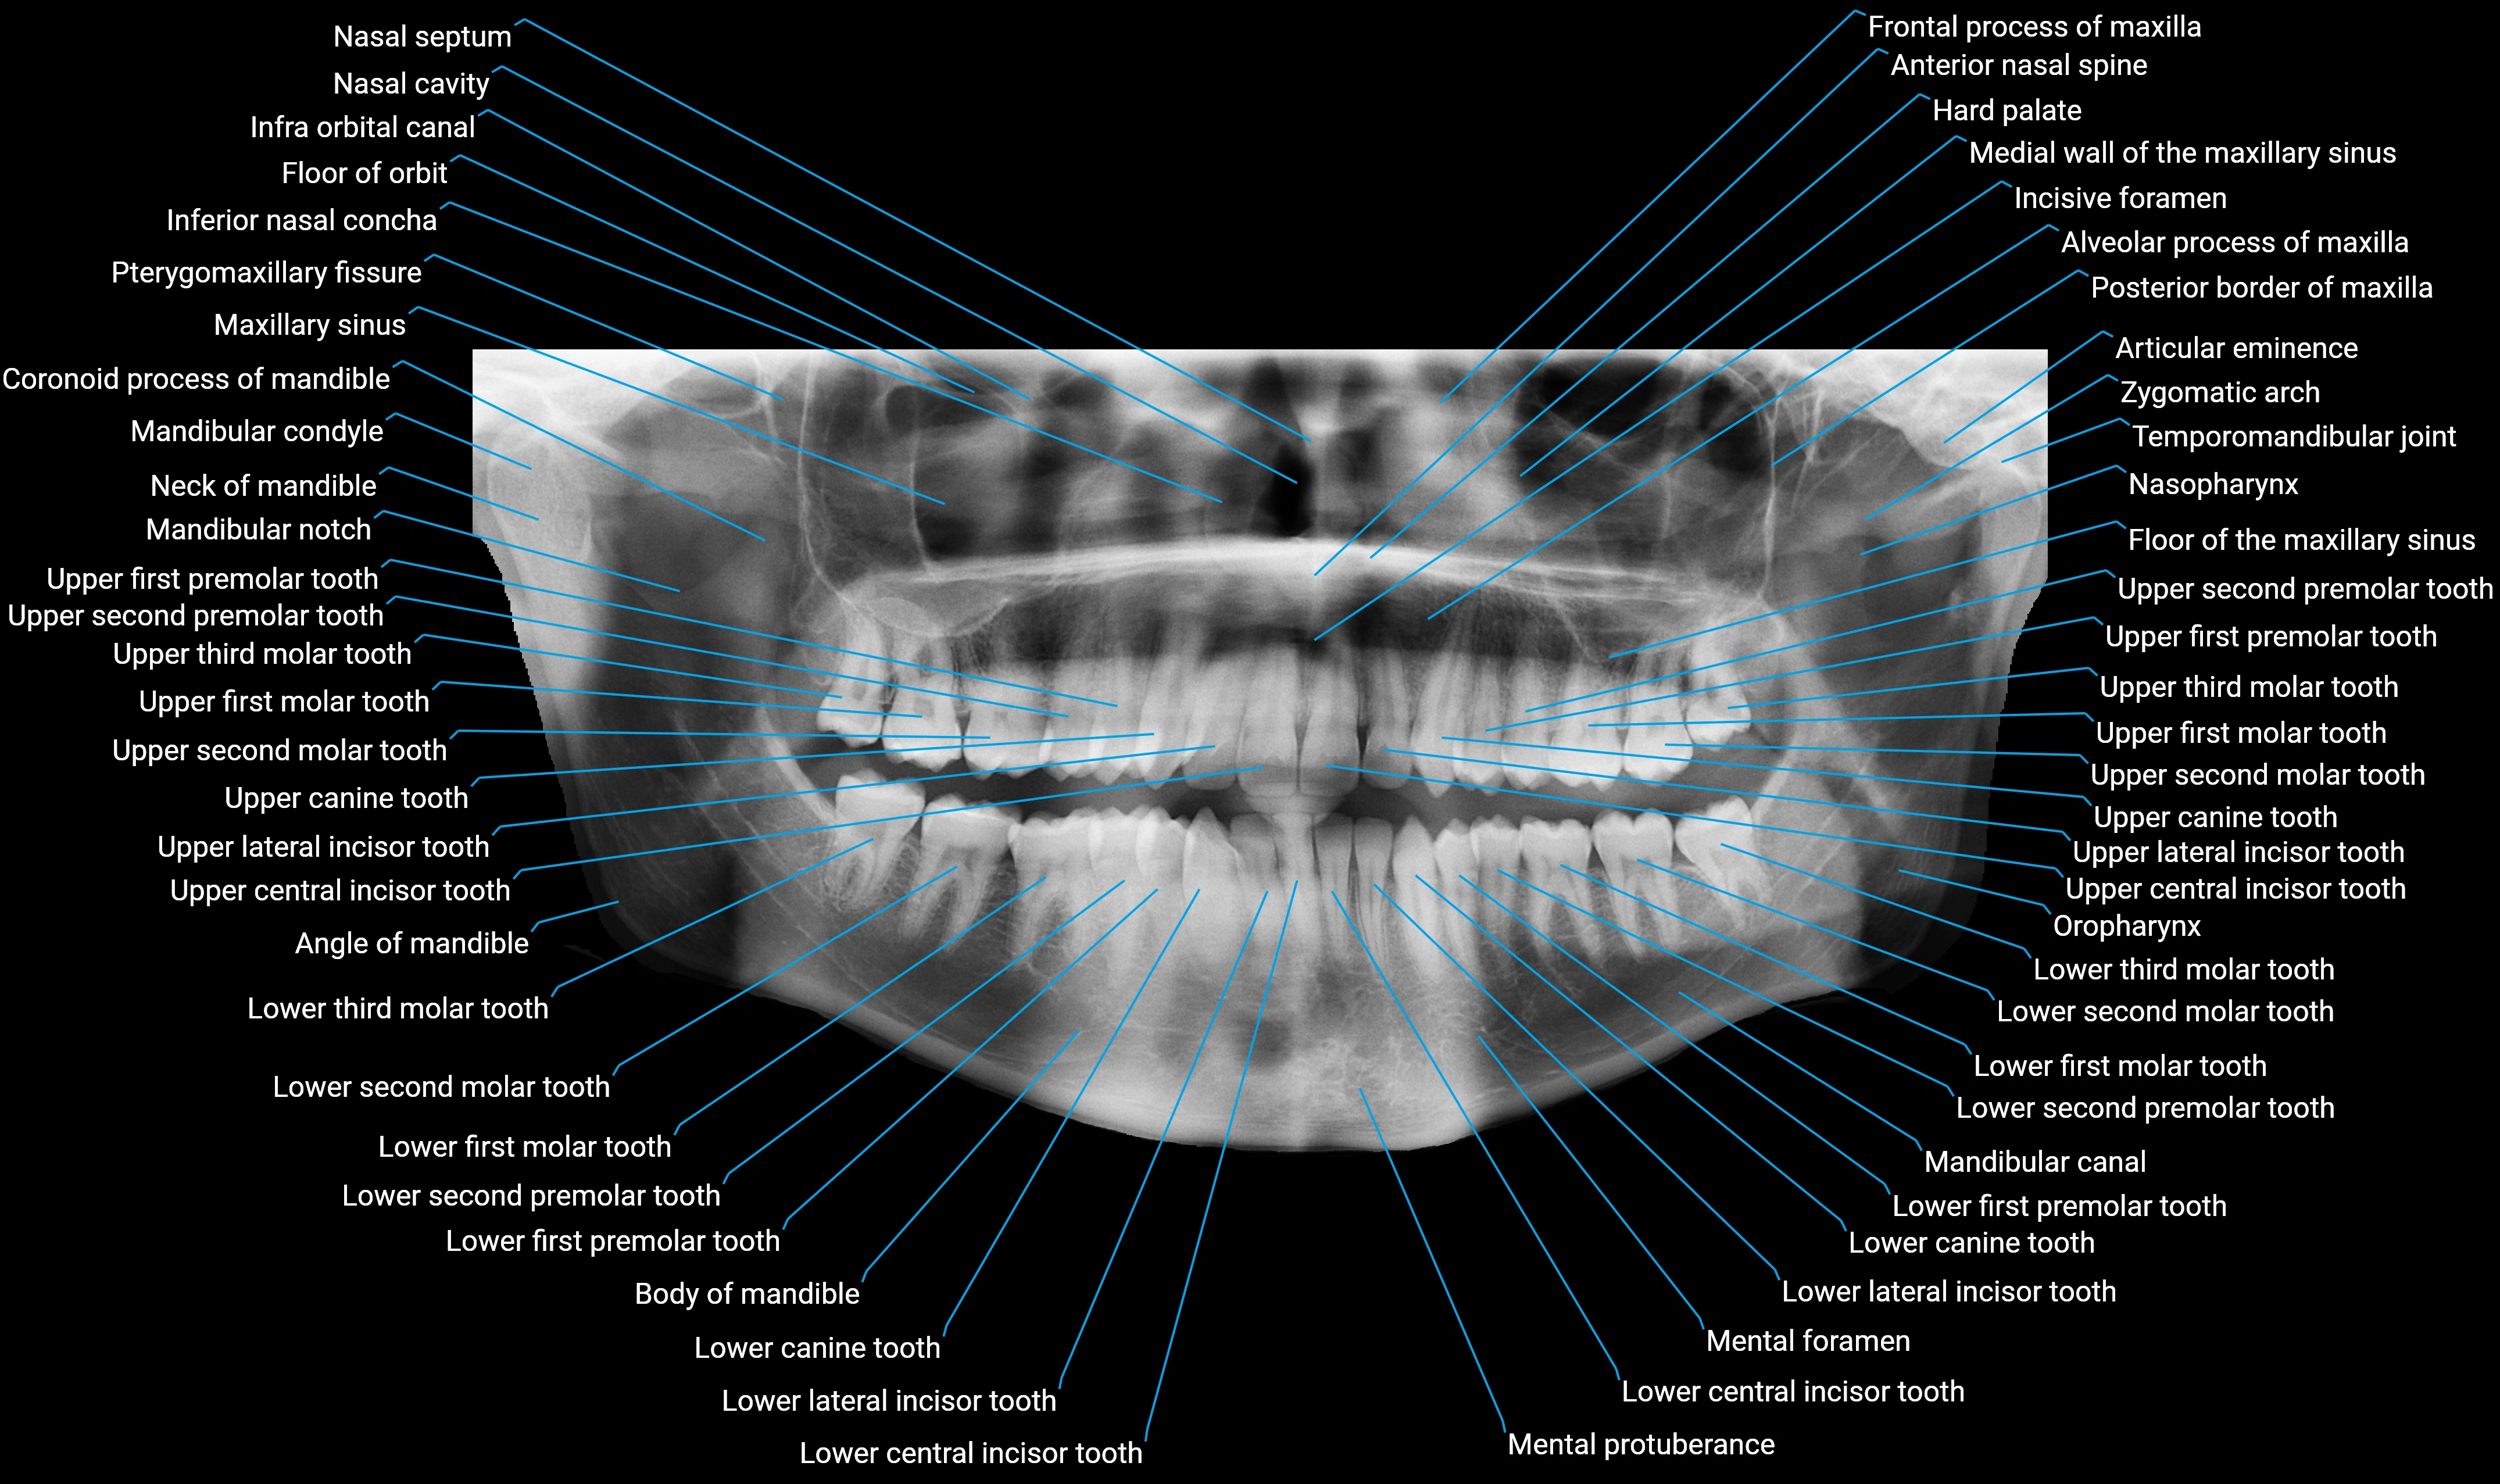

Alveolar process of maxilla

The alveolar process of the maxilla is the bony ridge of the maxilla that houses the upper teeth, extending from the anterior nasal spine to the maxillary tuberosity posteriorly. It consists of compact cortical bone on its outer surfaces and trabecular (cancellous) bone internally, with alveolar sockets (dental alveoli) forming individualized cavities for each tooth. The alveolar process develops in association with tooth eruption and resorption, adapting its shape and volume throughout life. It also forms part of the hard palate medially and contributes to the architecture of the midface, supporting the upper lip, cheeks, and nasal floor.

• Houses and supports the maxillary teeth

• Provides attachment for the periodontal ligament

• Contributes to midfacial structure and aesthetics

• Supports adjacent soft tissues including lips, cheeks, and nasal floor

• Facilitates mastication and occlusion